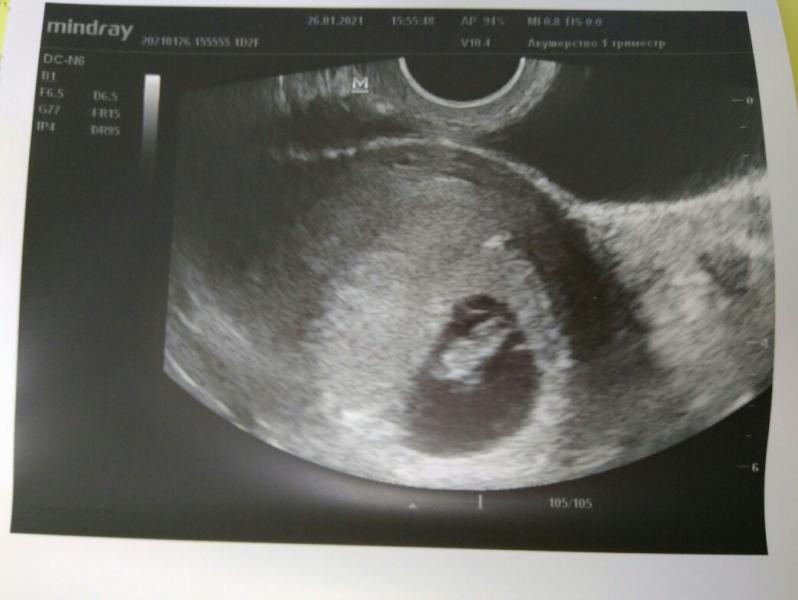

Прошел первый скрининг (ровно в 12 недель), все показатели отличные, ктр 5,4 см, идем точно в срок)

Малыш дисциплинированный, попросили не дергаться, так сразу замер и дал все замерить.

Предположили по половому бугорку мальчика, но на таком сроке сказала еще неточно, может уйти. Бывало ли у кого, что в итоге потом сказали девочку?))